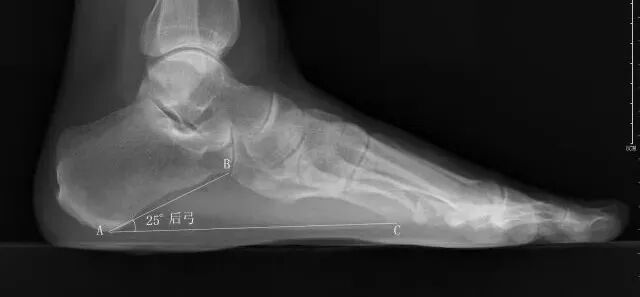

应负重条件下摄足正侧位X线片,主要在足侧位片测量足弓的角度改变。

跟骨角

• 正常值:男性28°~40°,女性25°~42°;

• 距跟后关节上缘和跟骨结节后上缘的连线与跟骨上关节面连线间的夹角;

• 跟骨角变小,提示有扁平足或跟骨骨折;角度增大,提示弓形足。